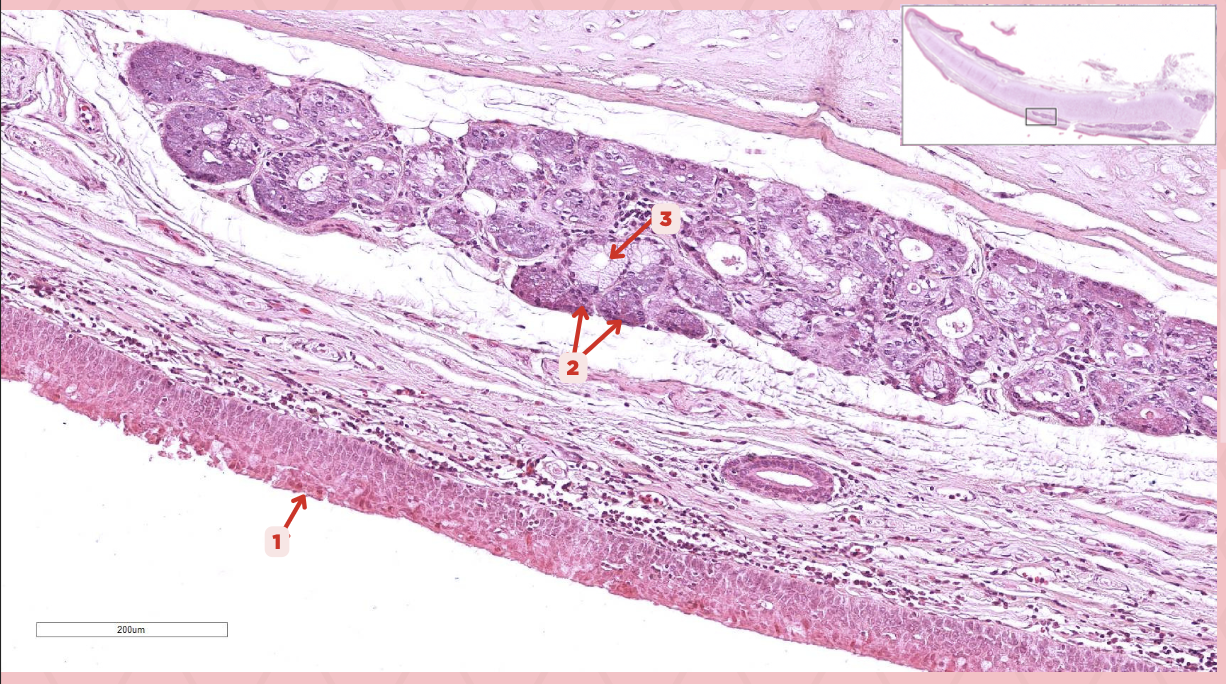

Identify the structure labeled as 1.

Laryngeal Ventricle

Space that separates the true and false vocal cords (#4)

True Vocal Cord

The #2 consists of a lamina propria that includes the vocalis ligament and a group of skeletal muscles known as the vocalis muscle.

Vocalis Ligament

Identify the structure labeled as 1.

True Vocal Cord

Identify the structure labeled as 2.

Vocalis Muscle

Identify the structure labeled as 3.

Laryngeal Ventricle

Identify the structure labeled as 4.

False Vocal Cord

Identify the structure labeled as 5.